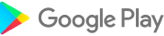

“ Anatomy 3D Atlas”通過其用戶友好和直觀的界面徹底改變了您研究人類解剖結構的方式。您可以從任何角度檢查每個解剖結構,這要歸功於高度紋理高達4K的質地的高度詳細的3D模型。該應用程序的組織按地區和預定義的觀點簡化了對單個部分或系統組以及不同器官之間的關係的研究。

特徵

- 簡單直觀的界面

- 在3D空間中旋轉並縮小每個型號

- 隱藏或隔離單個或多個選擇模型的選項

- 過濾以隱藏或顯示每個系統

- 搜索功能可以輕鬆找到每個解剖部分

- 書籤功能以保存自定義視圖

- 智能旋轉自動移動旋轉中心

- 透明度函數

- 通過從淺表層到最深的肌肉的肌肉可視化肌肉

- 通過選擇模型或引腳,相關的解剖術語顯示

- 肌肉的描述:起源,插入,神經和動作

- 顯示/隱藏UI接口(小屏幕非常有用)

Anatomy 3D Atlas應用截圖